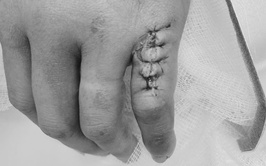

Với sự phát triển mạnh mẽ của y học hiện đại, các kỹ thuật điều trị sỏi tiết niệu đã có bước tiến vượt bậc, mang lại nhiều lựa chọn điều trị an toàn, ít xâm lấn và hiệu quả cao cho người bệnh. Tại Bệnh viện Thận Hà Nội, trung tâm chuyên khoa đầu ngành về thận - tiết niệu của Thủ đô, việc triển khai thường quy các kỹ thuật tán sỏi tiên tiến đang mở ra cơ hội điều trị tối ưu cho hàng ngàn bệnh nhân mắc bệnh lý sỏi tiết niệu.